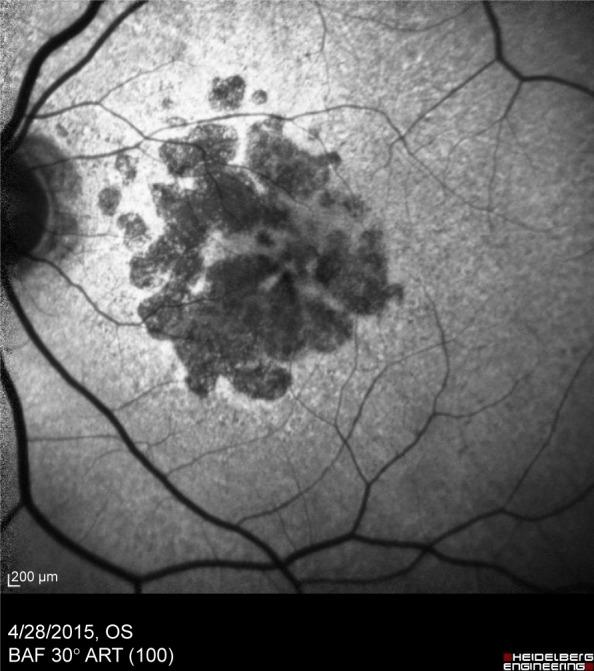

Age-related macular degeneration (AMD) is the leading cause of irreversible central vision loss in developed countries. With the aging of population, AMD will become globally an increasingly important and prevalent disease worldwide. It is a complex disease whose etiology is associated with both genetic and environmental risk factors. An extensive decline in the quality of life and progressive need of daily living assistance resulting from AMD among those most severely affected highlights the essential role of preventive strategies, particularly advising patients to quit smoking. In addition, maintaining a healthy diet, controlling other risk factors (such as hypertension, obesity, and atherosclerosis), and the use of nutritional supplements (antioxidants) are recommendable. Genetic testing may be especially important in patients with a family history of AMD. Recently, unifying criteria for the clinical classification of AMD, defining no apparent aging changes; normal aging changes; and early, intermediate, and late AMD stages, are of value in predicting AMD risk of progression and in establishing recommendations for the diagnosis, therapeutic approach, and follow-up of patients. The present review is focused on early and intermediate AMD and presents a description of the clinical characteristics and ophthalmological findings for these stages, together with algorithms for the diagnosis and management of patients, which are easily applicable in daily clinical practice.

年龄相关性黄斑变性(AMD)是发达国家不可逆性中心视力丧失的主要原因。随着人口老龄化,AMD在全球范围内将成为日益重要且普遍的疾病。它是一种复杂疾病,其病因与遗传和环境风险因素均有关联。在受影响最严重的人群中,AMD导致生活质量大幅下降以及对日常生活协助的需求不断增加,这凸显了预防策略的重要作用,尤其是建议患者戒烟。此外,保持健康饮食、控制其他风险因素(如高血压、肥胖和动脉粥样硬化)以及使用营养补充剂(抗氧化剂)都是可取的。基因检测对于有AMD家族史的患者可能尤为重要。最近,统一AMD临床分类标准,明确无明显衰老变化、正常衰老变化以及AMD的早期、中期和晚期阶段,对于预测AMD进展风险以及为患者的诊断、治疗方法和随访制定建议具有重要价值。本综述聚焦于早期和中期AMD,描述了这些阶段的临床特征和眼科检查结果,以及适用于日常临床实践的患者诊断和管理算法。